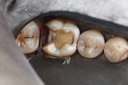

Mark Chun #14 pre-op